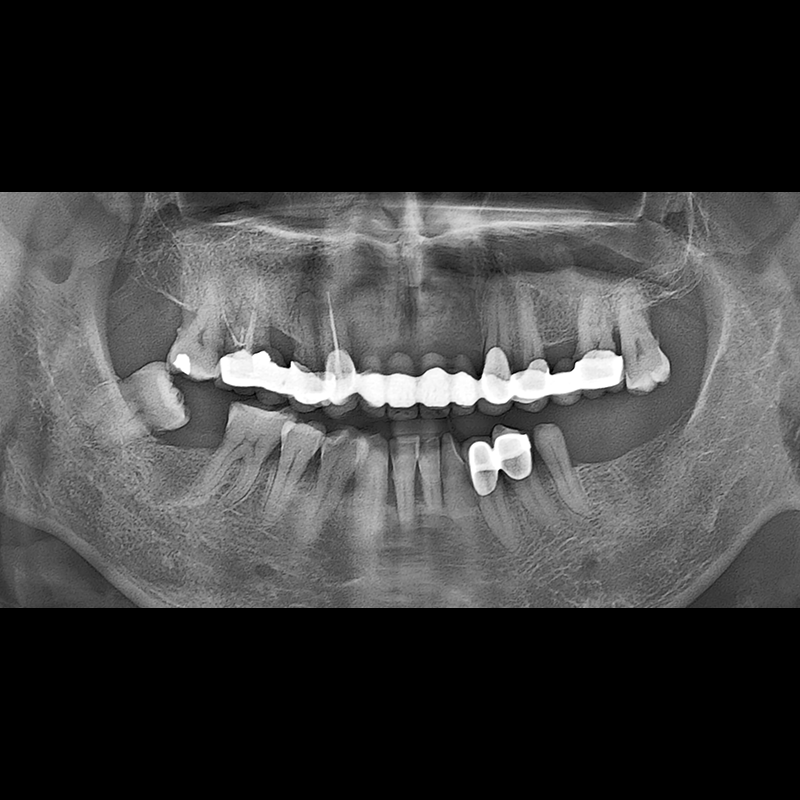

BEFORE AFTER

임플란트 전후사진 2025.05.30

결손된 치아 부분과 살리기 힘든 치아 위치에 임플란트를 식립하였습니다.